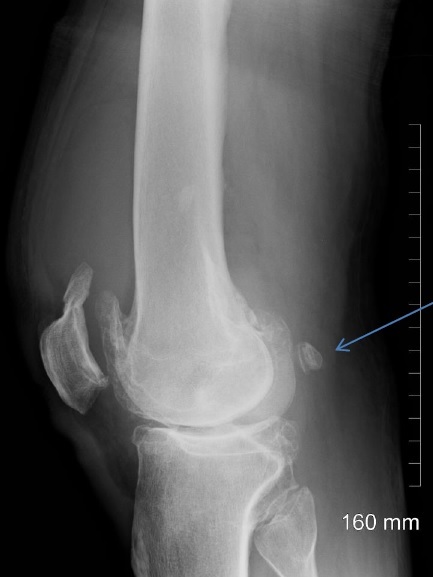

Fabella

Lipohemarthrosis